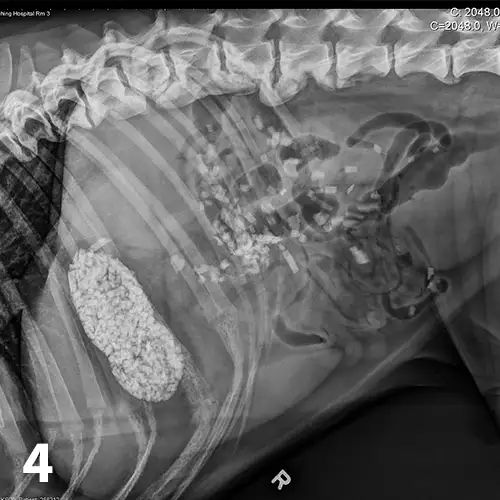

CBC reveals a leukocytosis (19.34 103/L; range, 5.10-14.00) characterized by a lymphocytosis (5.5 103/L; range, 1.4-4.6) and a mature neutrophilia (13.10 103/L; range, 2.65-9.80) with a mild thrombocytopenia (171 103/L; range, 147-243). A pancreatic-specific lipase is elevated (580 g/L; range, 0-200 g/L) and consistent with pancreatitis. Abdominal radiographs (Figures 1-3; See below) reveal a moderately distended stomach that contains a large number of irregularly shaped mineral opacities. Additional mineral opacities are present in multiple small intestinal segments as well as the colon. There is also a mild decrease in serosal detail in the mid-abdominal region.

Abdominal radiographs, repeated 14 hours later, reveal minimal aboral movement of the mineral opacities (Figures 4 and 5; see below).